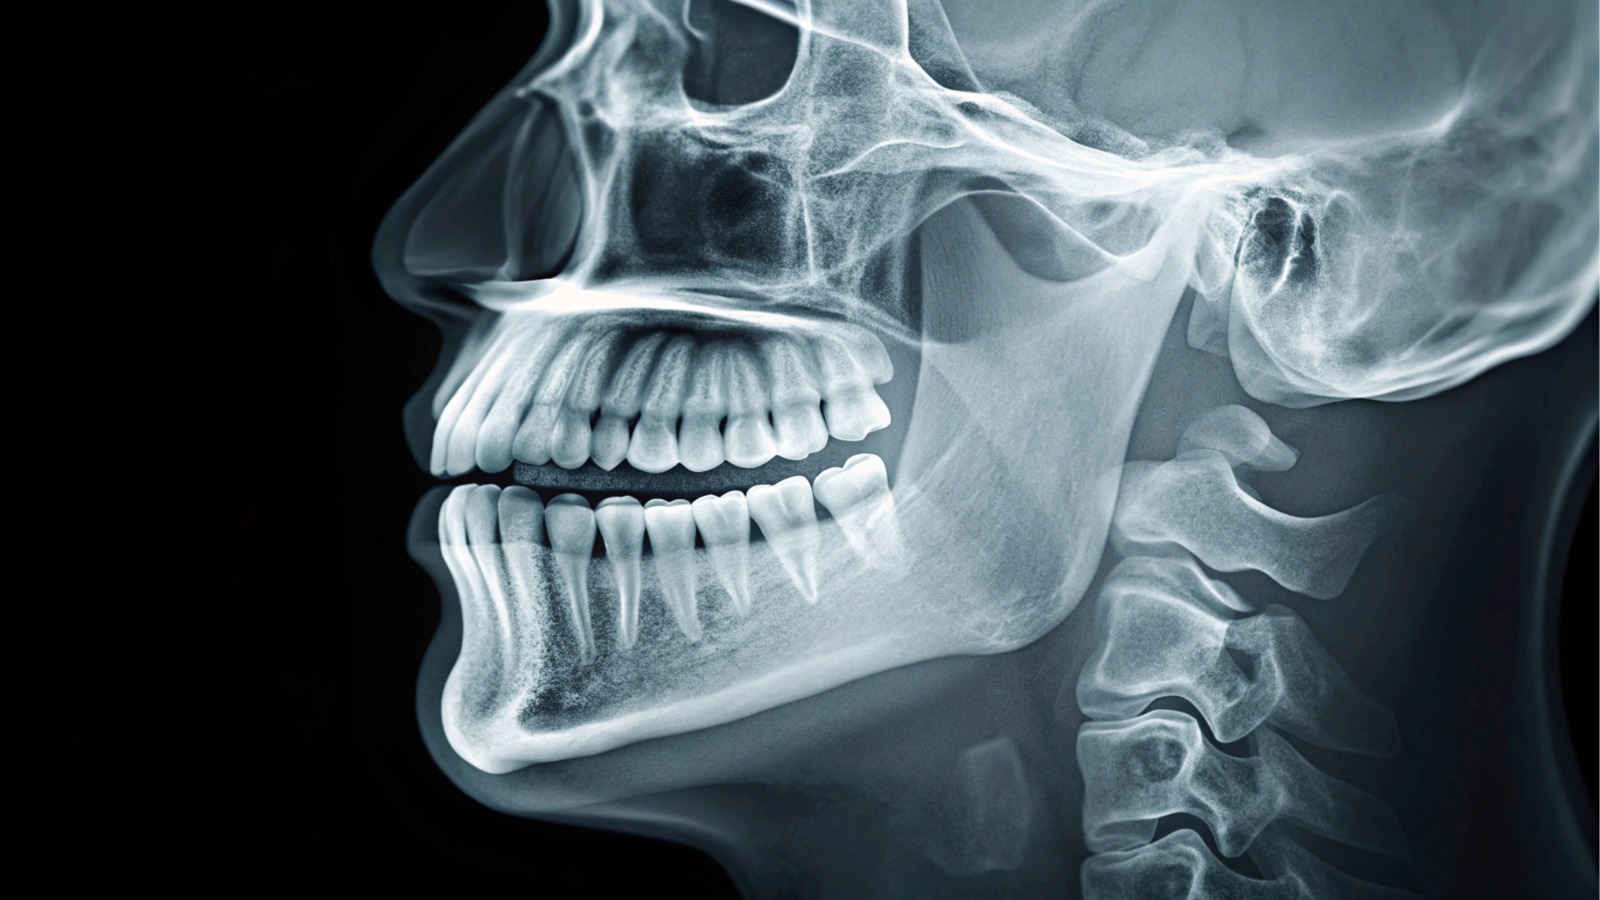

What Is a Cephalometric (Ceph) X-Ray?

A cephalometric X-ray is a standardized, side-view (lateral) dental radiograph of the head and face. It captures the skull, jaw bones, teeth, facial profile, and airway in a single image. Ceph X-rays are most commonly used in orthodontics because they allow for precise evaluation of how the teeth, jaws, and facial structures relate to one another.

What Can Be Seen on a Cephalometric X-Ray

A cephalometric X-ray offers detailed insight into facial and dental alignment, including:

- Position and angulation of teeth

- Upper and lower jaw relationships (maxilla and mandible)

- Facial skeletal structure and overall profile

- Bite discrepancies such as overbite, underbite, and open bite

- Growth patterns of the face and jaws

- Airway space assessment

- Soft tissue profile, including lips, chin, and nose outline